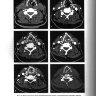

Примеры страниц из книги "Визуализация заболеваний шеи" - Труфанов Г. Е., Припорова Ю. Н.